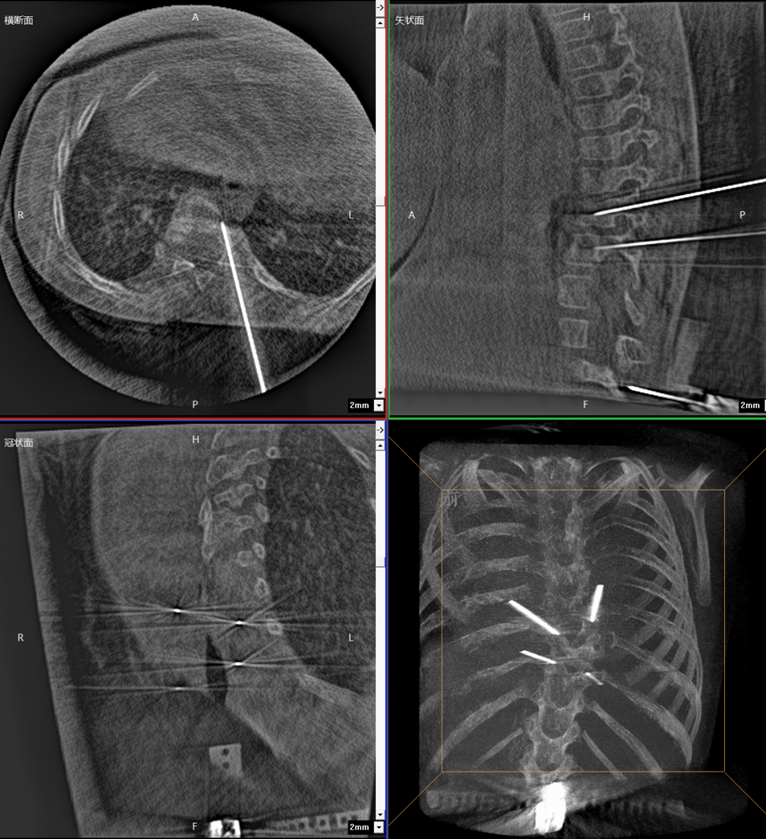

During the surgery, the medical team used the Perlove Medical’s flat-panel 3D C-arm to acquire 3D and CT-like images of the patient, enabling comprehensive visualization of the pedicles. Guided by the robot's 3D planning system, the surgeon mapped each screw's ideal path and angle to achieve maximum screw purchase strength and improve spinal stability by accommodating the unique biomechanical properties of pediatric bone tissue.

One-time planning for quadruple K-wire insertion

The robotic arm enhanced stabilization of surgical instruments, enabling precise execution. Guided by pre-planned trajectories, the system achieved accurate single-attempt pedicle screw placement within narrow vertebral pedicles - effectively navigating the 'anatomical labyrinth'. This approach eliminated risks associated with repeated positioning attempts. The fully integrated system demonstrated perfect coordination, successfully completing the implantation of four pedicle screws with sub-millimeter accuracy.

Fluoro-verified precise K-wire insertion

Addressing common parental concerns about radiation exposure, traditional K-wire insertion requires separate AP/lateral imaging for each of the four insertion points - with repeated X-ray verification. In contrast, the orthopedic robot utilizes a 'single 3D scan for complete trajectory planning' protocol. When integrated with Perlove Medical's 3D C-arm pulsed fluoroscopy mode, this approach significantly reduces total radiation dosage, effectively mitigating radiation risks.